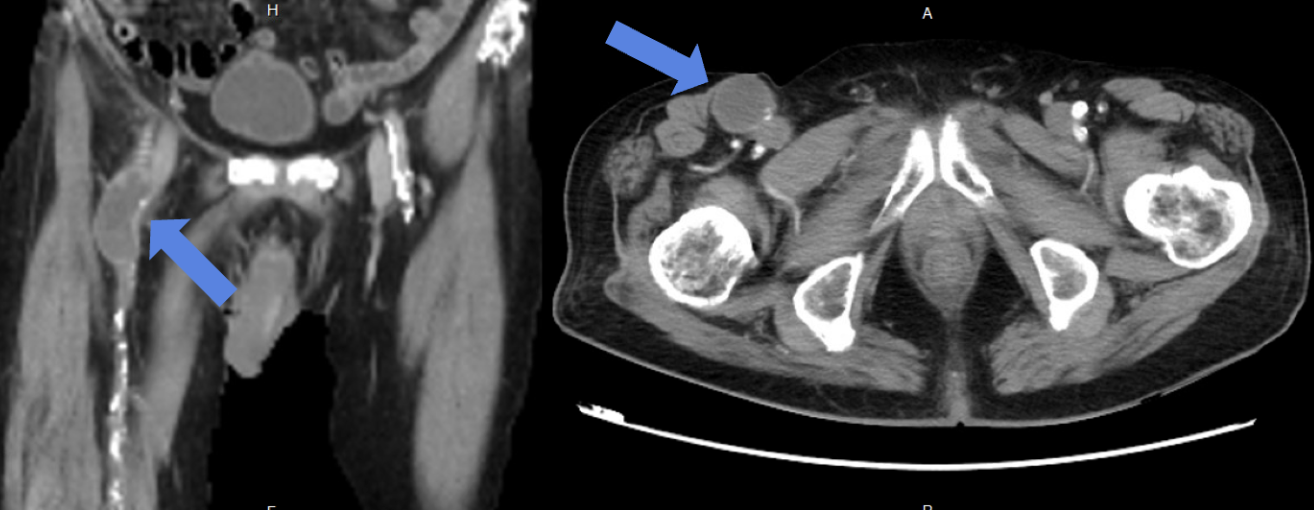

Relevant Test Results Prior to Catheterization

Lab data showed leukocytosis and significantly elevated C-Reactive Protein, alongside deteriorated renal function. Vascular Duplex showed monophasic flow and a hematoma near the Common Femoral Artery (CFA). CTA revealed Severe PAOD via extensive total occlusion from the right right External Iliac Artery (EIA) to the Superficial Femoral Artery (SFA), and a thrombosed aneurysm at the femoral bifurcation, and extensive Deep Venous Thrombosis (DVT) extending from the femoral vein distally.

The angiography confirmed extensive Chronic Total Occlusion (CTO) of the right External Iliac Artery (EIA), Common Femoral Artery (CFA), and proximal Superficial Femoral Artery (SFA). The limb's circulation was critically dependent on collateral flow: the Deep Femoral Artery (DFA) was patent and supplying the distal SFA. Distally, a 50% stenosis was noted in the Popliteal Artery, but the Below-the-Knee (BTK) arteries were patent.